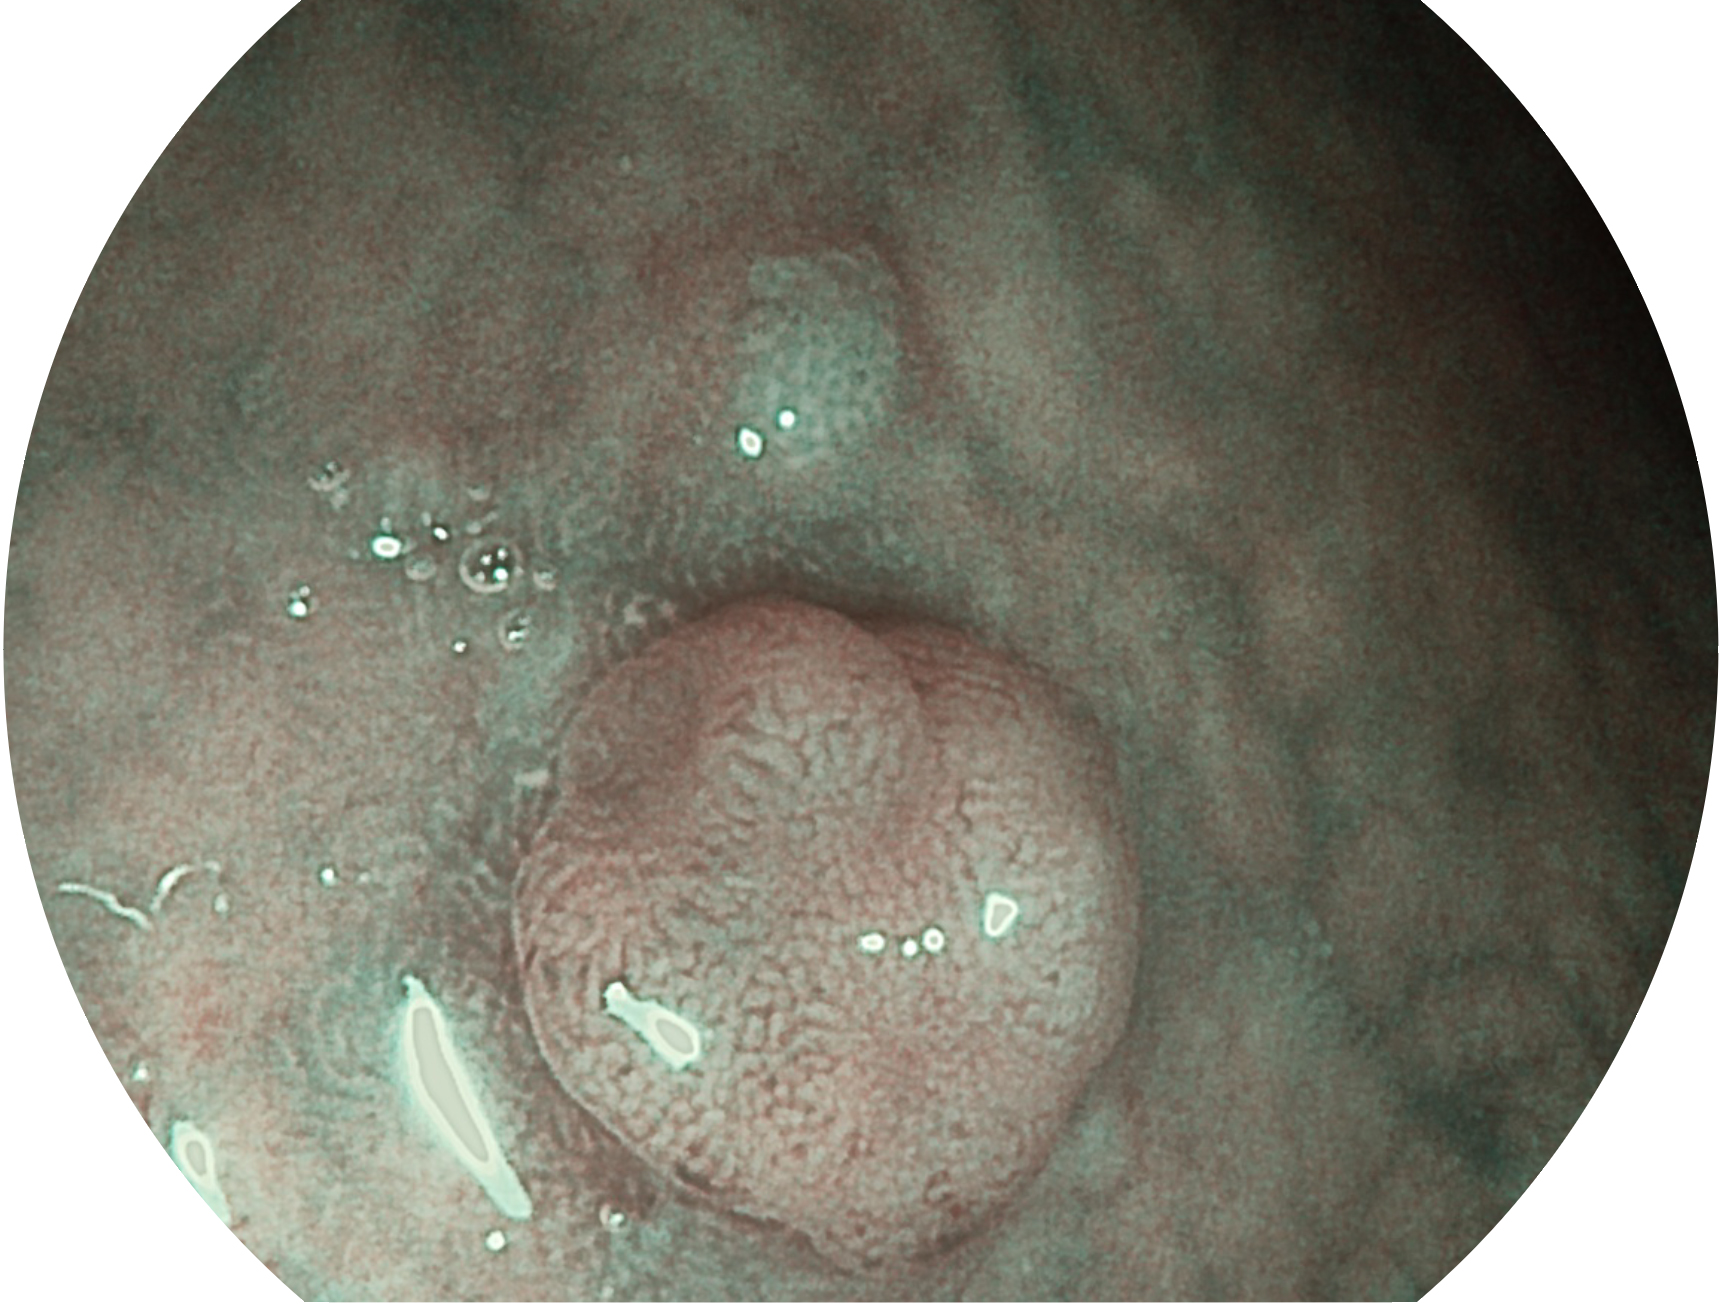

米兰官方网站新开发的内镜染色技术,主要是基于多波长LED 光源的开发,VLS-55Q 四波长LED 光源是由四个不同颜色的LED光按照相应照明模式所规定的特定发光比例进行合束后形成,合束后形成的照明光的光谱由红光、绿光、蓝光及蓝紫光这四个不同的波段范围构成。具有更高光谱自由度,通过光谱比例的控制,实现了聚谱成像技术,英文全称为“Spectral Focused Imaging, SFI”,缩写为“SFI”和光电复合染色成像技术,英文全称为“Versatile Intelligent Staining Technology, VIST”,缩写为“VIST”。